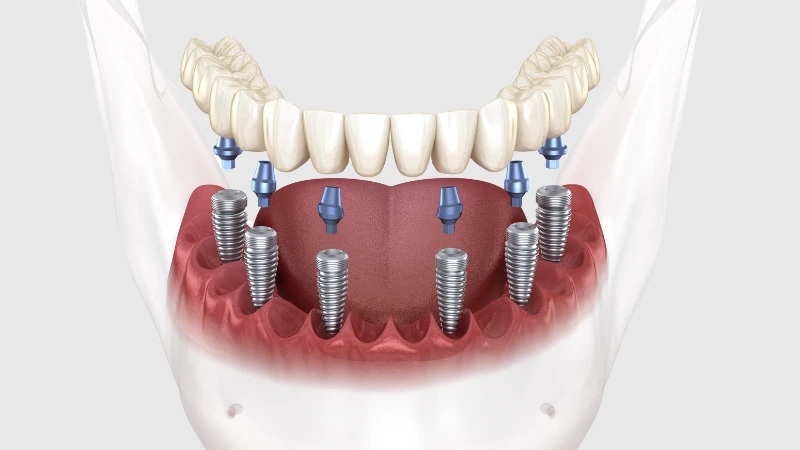

All on 6

All on 6 si riferisce all’impianto chirurgico di sei impianti nella mascella superiore e inferiore. I due impianti dentali aggiuntivi di all-on-4 potrebbero essere necessari per garantire stabilità e forza in bocca, aumentando le probabilità di successo della tua nuova protesi permanente. Per quei pazienti in cui la carie dell’osso mascellare rappresenta un problema, l’impianto dentale all on 6 offre ulteriore rafforzamento e stimolazione all’osso mascellare. I nostri dentisti esperti ti consiglieranno ciò che è meglio per le tue esigenze.